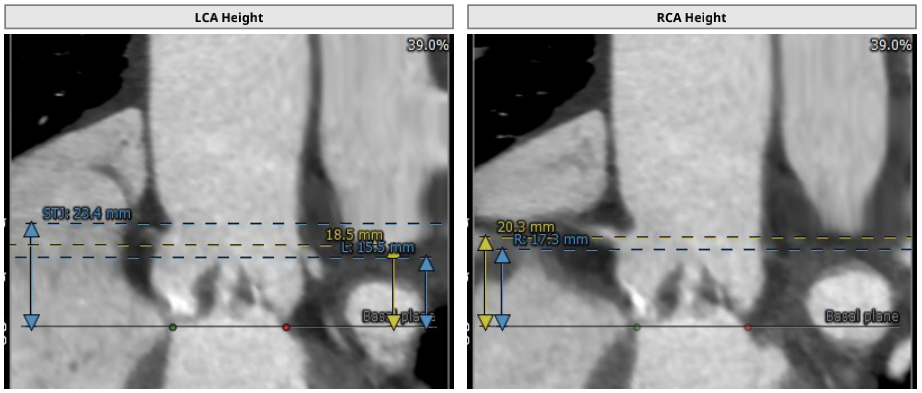

术前CT结果显示,主动脉瓣口面积498.2mm²,瓣环平均直径25.4mm,瓣环周长80.43mm;LVOT面积523.8 mm²,LVOT平均直径25.8mm;升主动脉平均直径29.2 mm;心夹角44°;左冠开口高度15.5mm、右冠开口高度17.3mm。

患者Type 0型二叶瓣,重度钙化,冠脉三支病变,左右冠脉开口高度15.5mm/17.3mm,左主干开口内侧较低,手术策略选择需综合考虑以下因素: